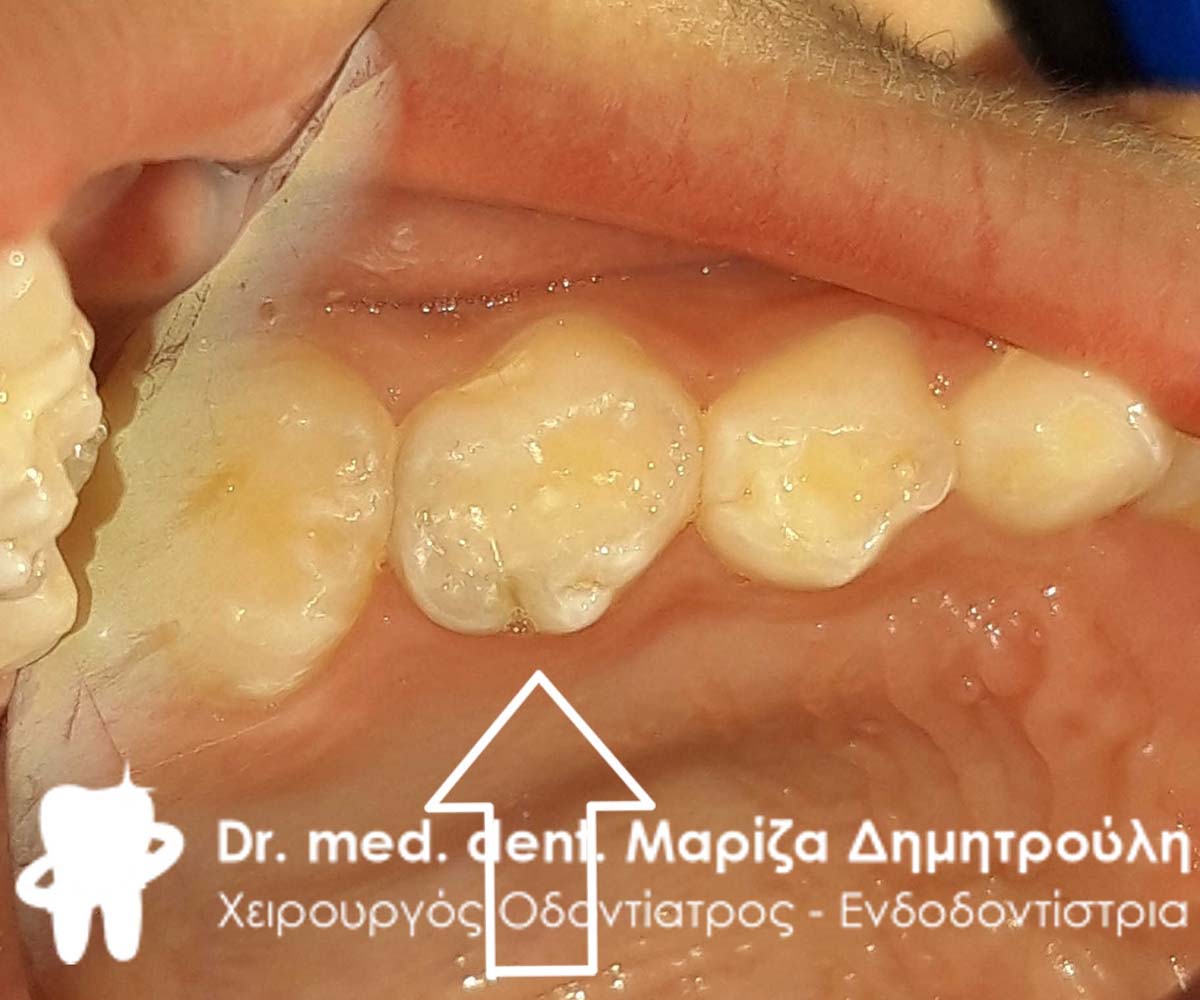

Ο ασθενής παραπονιέται για πόνο κατά τη μάσηση στη δεξιά πλευρά της άνω γνάθου. Η κλινική εξέταση αποκάλυψε δύο μικρές τερηδονικές κοιλότητες, οι οποίες αποκαταστάθηκαν με λευκό σφράγισμα ρητίνης.

ΠΡΙΝ

ΜΕΤΑ